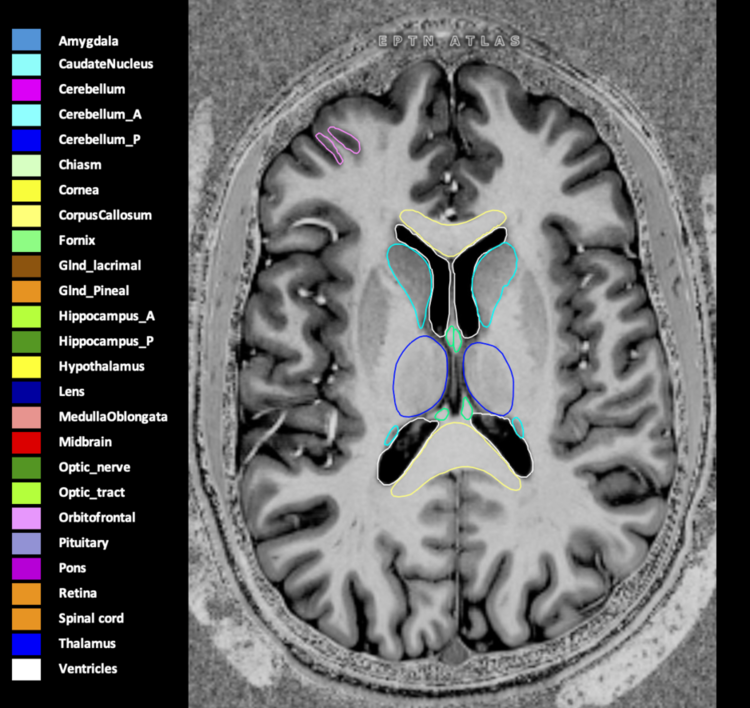

Included are all OARs known to be relevant for radiation-induced toxicity in neuro-oncology: brain, brainstem (midbrain, pons, medulla oblongata), chiasm, cerebellum (anterior & posterior), cochlea, cornea, hippocampus (anterior & posterior), hypothalamus, lens, lacrimal gland, optic nerve, pituitary, skin, and vestibular & semicircular canals. To further facilitate research on cognition, vision and radiological changes after irradiation of the brain, potential clinically-relevant OARs are included: amygdala, caudate nucleus, cerebellum (anterior & posterior), corpus callosum, fornix, macula, optic tract, orbitofrontal cortex, periventricular space (PVS), pineal gland, and thalamus.

Three-dimensional delineation of the 25 consensus OARs for neuro-oncology are shown on CT (WW/WL 120/40, 3000/600), 3T MR images, (T1Gd, T2FLAIR 1mm) and 7T MR (MP2RAGE 0.7 mm). All are presented in transversal, sagittal and coronal view.